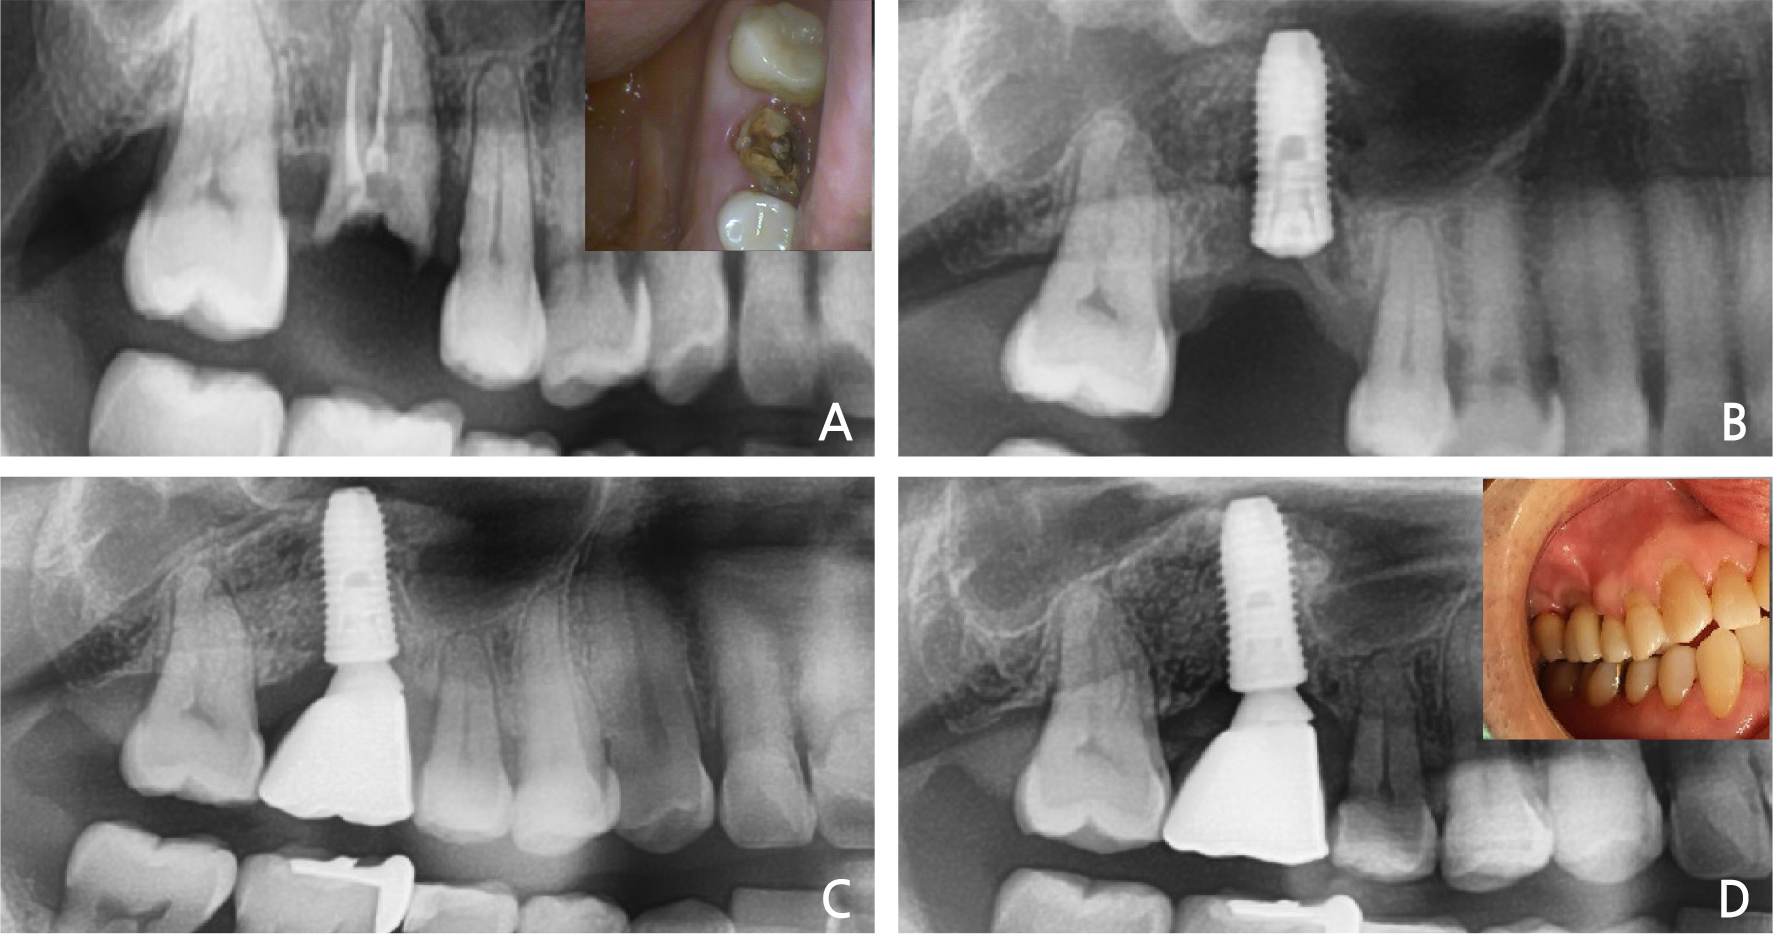

8. Case 8

A 50-year old man visited our clinic because of a fractured right maxillary 1st molar. Clinical and radiographic evaluations showed a decayed residual sinus-invading root (Fig. 8A). After extraction of the residual root, the immediate implant placement was performed with sinus elevation (Fig. 8B). During extraction, the crest area of the buccal bone plate was fractured. The fixture was placed slightly in the palatal area. Primary stability was attained from the inferior sinus wall and intact septal bone. After 3 months, loading was initiated, and a slight recession of the buccal area was observed (Fig. 8C). In radiographic view of 3-years follow-up, it was observed that the normal condition was maintained (Fig. 8D).